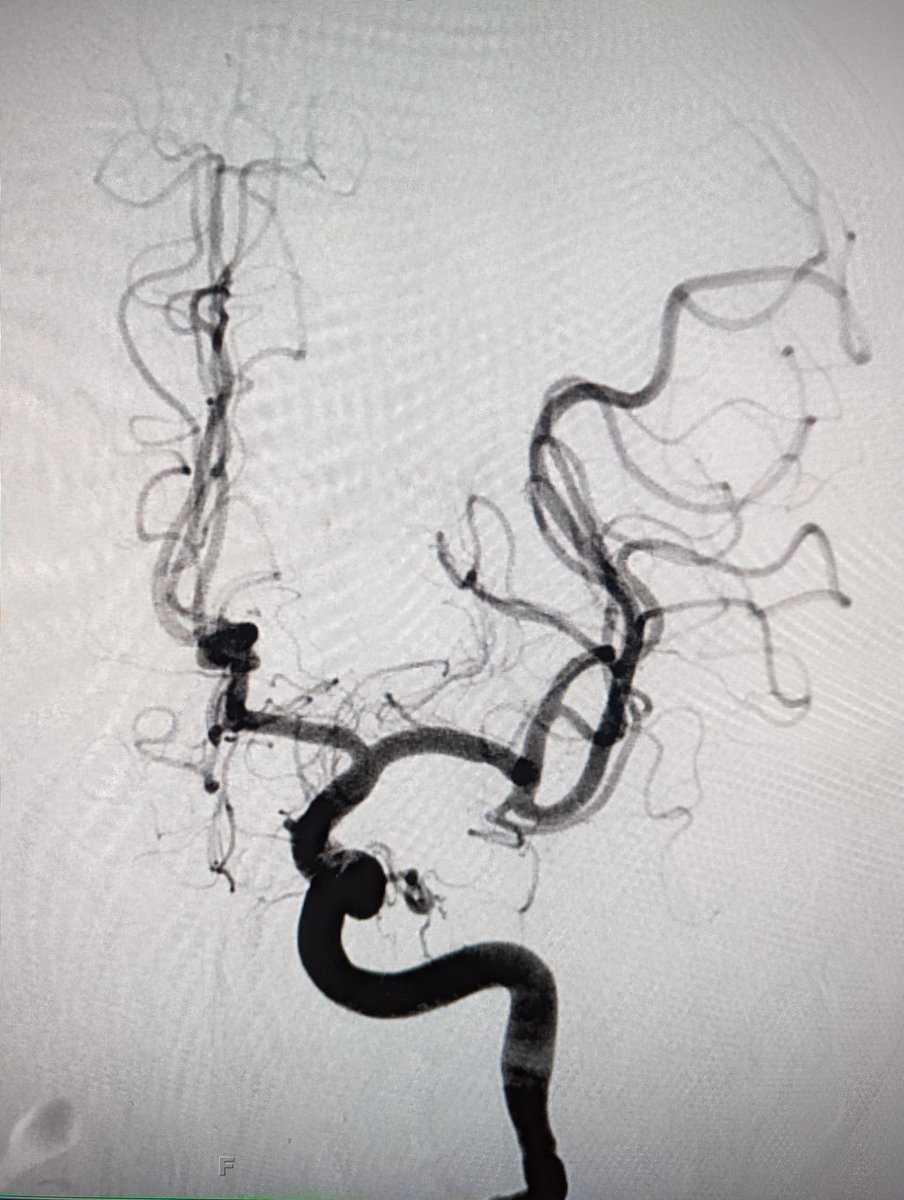

Neuro IR in Minneapolis. Proud product of UCSF. Husband to a Queen, father of 4 princesses. Die hard Buckeyes fan. Work hard, play harderr.